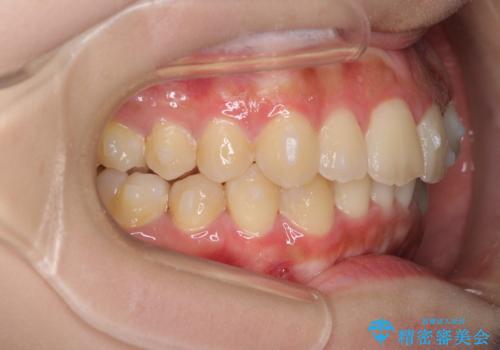

前歯のガタガタを目立たない装置でなおしたい インビザラインによる目立たない矯正

- 目立たない装置でガタガタをきれいにしたいとのご希望で来院されました。

インビザラインで矯正することとなりました。

左上の前から2番目の歯が通常とは異なる形態をしており、左右対称にすることはできませんでしたが、インビザラインで周りに気づかれることなく矯正治療をおえることができ、満足していただけました。